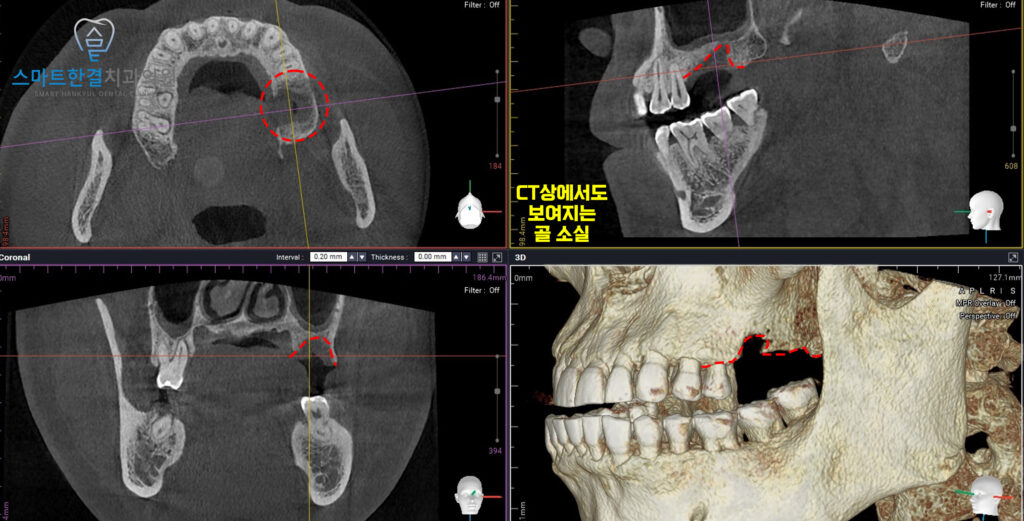

이후 임플란트 식립 전,

정밀한 확인을 위해

CT를 촬영했는데요.

촬영 결과,

수직적, 입 천장쪽으로

골 소실이 심각하게 진행된

상태로 확인되었어요.

임플란트만 식립하기에는

뼈의 지지력이 부족해,

추가적인 뼈이식이 필요함을

알 수 있었어요.